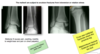

Lable the image:

what veins are shown

what are the dilated regions?

what muscles does the venous plexus in the R image sit between?

Left image:

- top = femoral vein

- popliteal vein

Right image:

- Posteior tibial vein draining into popliteal

- Peroneal/ Fibular vein draining into popliteal

The dilated regions shown in the venogram are the one way valves.

Venous plexus sat inbetween the two heads of gastrocnemius and soleus muscles.